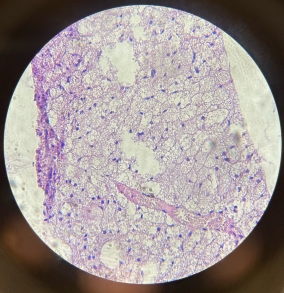

Lungs

Lungs

Lungs

Lungs

Lungs

Lungs

Lungs